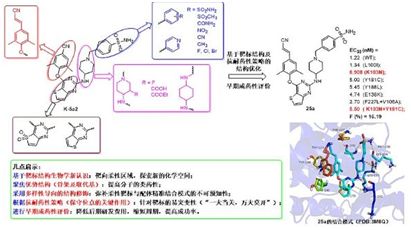

5.抗艾滋病药物新进展:山东大学药学院发现新一代高效抗耐药性 HIV- 1 抑制剂

doi:10.1021/acs.jmedchem.7b00332

以最新一代抗艾滋病药物依曲韦林为先导化合物,山东大学药学院药物化学研究所的刘新泳教授课题组与比利时 Leuven 大学医学院微生物与免疫学研究所合作,发现了一类对 HIV- 1 野生株及多数临床常见突变株均优于上市药物依曲韦林的噻吩并嘧啶类化合物,但美中不足的是,代表性化合物 K -5a2 对临床最常见的单突变株 K103N 以及双突变株 Y181C+K103N 的活性仍有待改善。为进一步提高对这两种临床最常见突变株的活性,该团队以 K -5a2 为先导化合物,根据靶标三维空间的适配性要求,特别是蛋白溶剂界面柔性区域的结构特征,综合运用基于靶标结构的合理药物设计及抗耐药性药物设计策略(形成主链氢键、精准靶向保守型氨基酸等),依次对其右翼、中心杂环和左翼进行了系统的结构修饰,以探讨未知的化学空间,并完善该类抑制剂的构效关系;采用多样性导向的结构修饰,可克服柔性靶标与配体精准结合模式的不可预知性;设计合成了多系列噻吩并嘧啶类 HIV-1 NNRTIs 并进行了细胞及靶点水平的生物活性测试以及早期成药性评价,最终发现多个对 HIV- 1 野生株及临床常见的严重耐药株均有纳摩尔水平抑制活性的化合物。

化合物 25a(DK5-1)具有抑制 HIV- 1 野生株和多种临床常见突变株的活性,较先导化合物 K -5a2 和依曲韦林均有大幅度提高。其中,抑制临床最常见的突变株 K103N 的活性(EC50= 0.908 nM)是 K -5a2 的 3 倍;尤其是抑制临床严重的双突变株 RES056(EC50 = 5.50 nM)的活性是 K -5a2 的 6 倍、依曲韦林的 3 倍。对单突变株 L100I、Y181C、Y188L 和 E138K,25a 的 EC50 值均小于 5.5 nM,远优于上市药物依曲韦林。初步的药代动力学试验显示 25a 在大鼠体内达峰时间为 1.7 小时,半衰期为 3.93 小时,并显示出良好的口服生物利用度(F = 16.19 %)。小鼠急性毒性试验表明,其 LD50> 2000 mg/kg,心脏毒性试验结果显示其抑制 hERG 钾离子通道的作用较低。目前正在对 25a 进行后续的成药性和临床前评价。

另外,本文作者还通过分子模拟分析了该类化合物的作用模式及抗耐药性机理。作者指出,除了 DAPY 类化合物经典的作用力之外,25a 的右翼磺酰胺基团可与蛋白溶剂界面的 Lys104 和 Val106 的主链之间形成关键氢键作用,左翼新引入的氰基乙烯基基团指向由高度保守氨基酸 Phe227 和 Trp229 组成的狭长通道,并与之形成紧密的疏水作用,这也是 25a 能对多数耐药株保持高效抑制活性的主要原因。该研究的一些启示对其他易突变型或配体结合位点高度柔性靶标的药物设计具有普遍的参考价值。